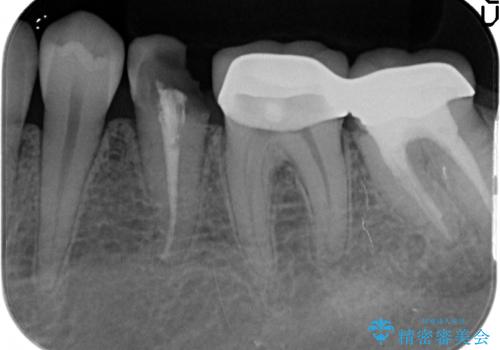

深い虫歯 歯周外科を併用した精度の高い補綴治療

- 治療途中で放置してしまった歯の治療の再開を希望され来院されました。

虫歯を除去すると、歯ぐきよりも深い虫歯であることが判明したため歯周外科を行い問題を解決していきます。